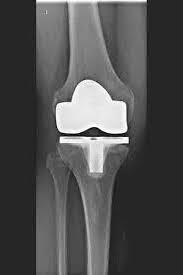

TKA (ARTIFICIAL KNEE JOINT)

The artificial knee joint replaces the cartilage surface that has been destroyed by osteoarthritis.

The underlying bone on the femur and tibial head remains intact. Some compare a modern artificial knee joint to a crowning of a tooth; the exact term is the so-called

bicondylar resurfacing. Between the new surfaces on the upper and lower leg is the so-called inlay made of a specially hardened white plastic, which can be seen in the X-ray image as the distance between the metal parts.